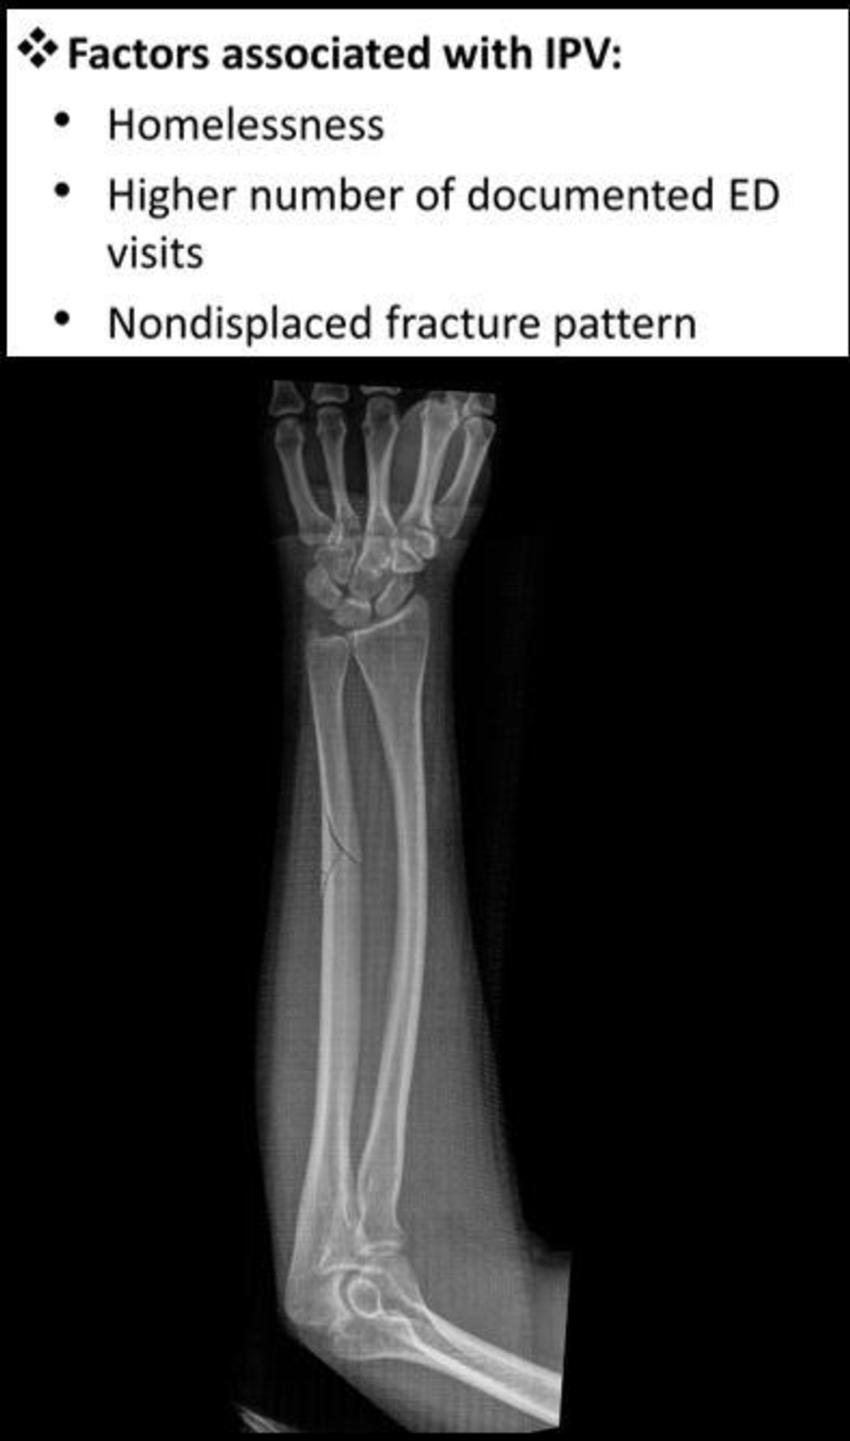

Figure 3. Factors associated with intimate partner violence: Homelessness, higher number of documented emergency department visits, and nondisplaced fracture pattern.

Confirmed cases were also linked with homelessness and previous visits to the emergency department with musculoskeletal injuries.

Analysis of the radiographs demonstrated that intimate partner violence was strongly associated with minimally displaced fractures.

“The radiological characteristics we were looking at were the location of the fracture, the pattern of the fracture in terms of how it broke, and the displacement of the fracture,” said study lead author David Sing, M.D., an orthopedic surgery resident at Boston Medical Center. “Out of all those things, what we usually saw was a minimally displaced fracture, meaning the bone is broken all the way through but has not shifted significantly.”